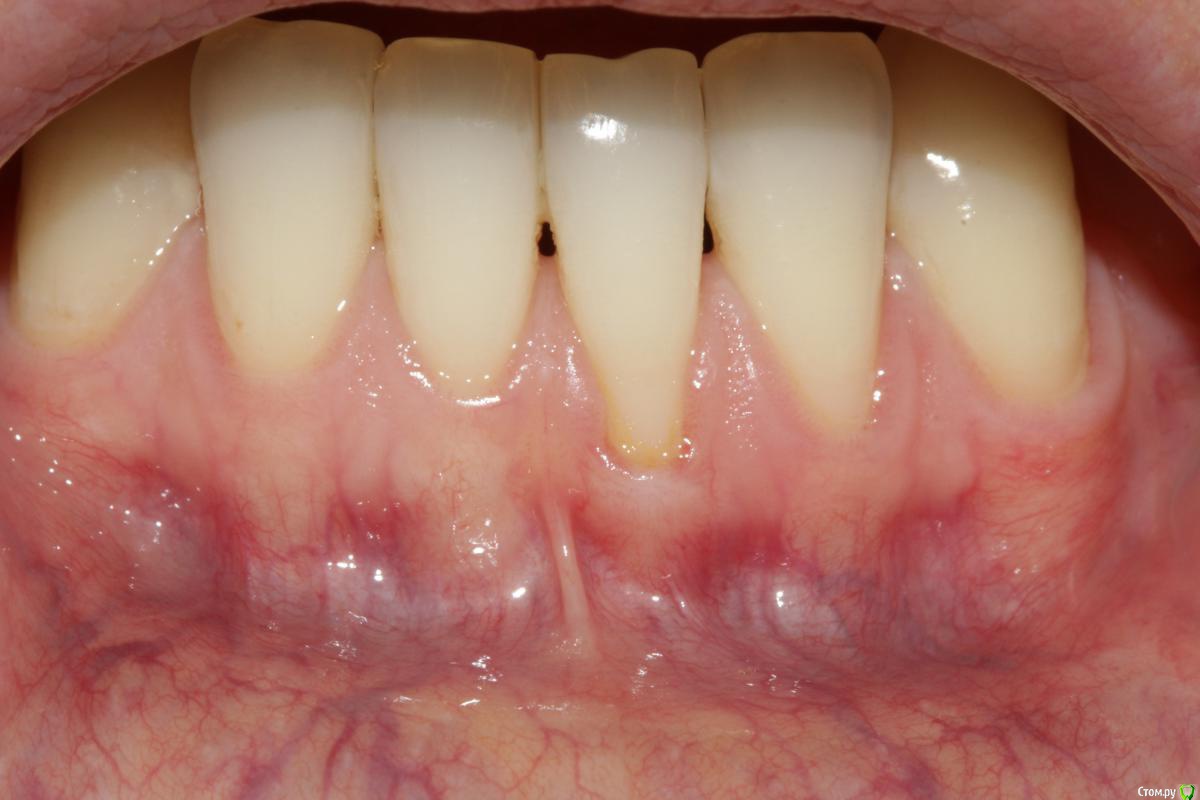

Dc.Petrov Опубликовано 18 сентября, 2015 Поделиться Опубликовано 18 сентября, 2015 Хочу узнать мнение коллег. Можно ли считать результат удовлетворительным? Рассчитывал на лучший итог. 15 Ссылка на комментарий

zzkz Опубликовано 19 сентября, 2015 Поделиться Опубликовано 19 сентября, 2015 через 3-6 мес можно точно сказать, на сегодня все нормуль. 31 еще можно подтянуть. Ссылка на комментарий

Dc.Petrov Опубликовано 21 сентября, 2015 Автор Поделиться Опубликовано 21 сентября, 2015 через 3-6 мес можно точно сказать, на сегодня все нормуль. 31 еще можно подтянуть.Считаете, что реально ещё подтянуть? Ссылка на комментарий

zzkz Опубликовано 22 сентября, 2015 Поделиться Опубликовано 22 сентября, 2015 До ЦЭС у 31 и 34 кажется что можно, по крайней мере по фото Ссылка на комментарий

zzkz Опубликовано 23 сентября, 2015 Поделиться Опубликовано 23 сентября, 2015 с 34 понятно, с ним поработаю . Просто на одном том же месте (31) есть ли смысл повторять ?если это возможно и нужно, конечно стоит. Можно даже и бесплатно. Я за повторную операцию беру только за расходник. Тут мне уже принципиально хочется добить рецессию)) Ссылка на комментарий